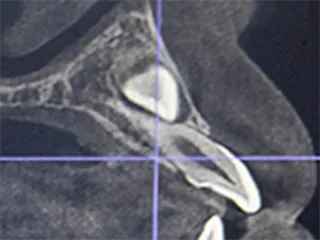

根管は一人ひとり形が違い、弯曲や側枝と呼ばれる入り組んだ構造も含まれており、どのような構造になっているかを正確に把握した上で、神経を精緻に処理をすることが重要です。

歯科用コーンビームCTを使用し、根管の内部を3次元的に解剖したように隅々まで構造を把握することで、歯髄を取る必要な部分がはっきり分かり、勘や経験に頼らず、的確に処置を進められます。